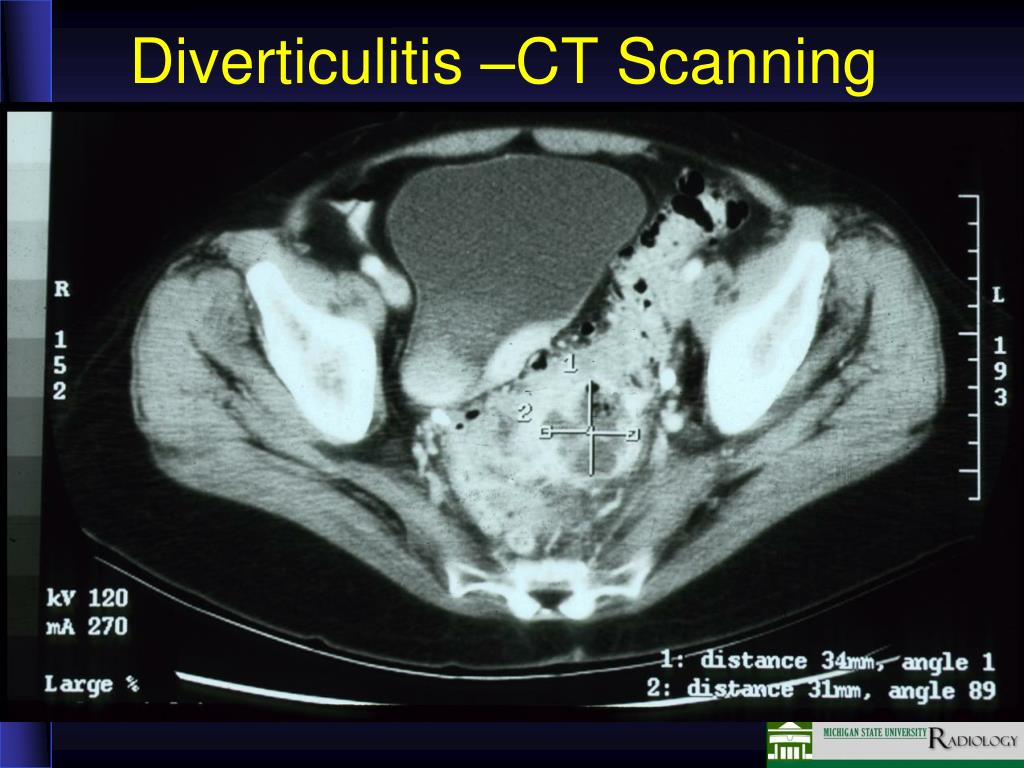

16. Diverticulitis –CT Scanning

15. CT of Diverticulitis • Inflammatory process in the mesentery (diffuse gray area) with air collections (arrows)